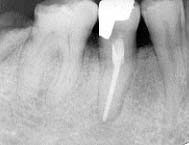

30歳 女性 2」 治療後Dental写真

初診時 パノラマ カリエス治療後の歯髄炎および根尖病巣

臼歯部に二次カリエスが認められるものの、清掃状態は比較的良好。歯槽骨の吸収も認められない。 10数年前に2」の治療(CR充填)を受けたのち、同部根尖付近の違和感を感じるものの放置。 数カ月前から歯肉の腫脹と疼痛が著明となり来院。

レントゲン診査の結果、2」の根尖病巣が認められたので、感染根管治療(失即充)を施行。 術後症状は暫時軽減し予後良好。

10数年前の治療後、切削時の発熱、またはCR(残留モノマー)充填の薬物刺激により歯髄が 炎症を起こし、変質(→腐敗)した結果根尖部に炎症が波及したものと思われる。